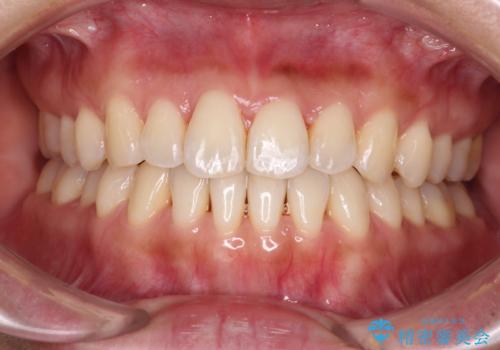

【モニター】前歯のデコボコをインビザラインで改善

- 前歯のデコボコで前方に出ていることを気にして来院された患者様です。

上顎前歯が捻れて前方に飛び出しており、下顎前歯もそれに沿うようにデコボコとなっていました。

IPR(歯と歯の間を削る処置)によりスペースを獲得して上下顎前歯のデコボコを改善し、飛び出している前歯が引っ込むように設定し、インビザラインにて矯正治療を行うこととしました。

装着時間を守ってくださったので、予定通りの期間で終えることができました。インビザライン特有の、奥歯の咬み合わせの問題もなく、しっかりと歯列を改善することができました。